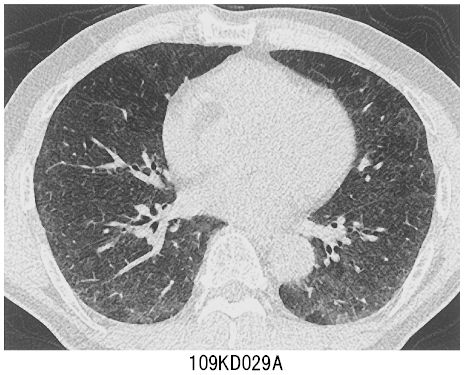

27歳の男性。強い咳嗽,発熱および呼吸困難を主訴に来院した。2か月前の初夏から咳嗽が出現し次第に増強した。1週前から発熱とともに呼吸困難が出現し,外来にて低酸素血症を認めたため入院となった。入院2日後には症状と低酸素血症とが改善し3日後に退院したが,退院翌日に再び咳嗽,発熱および呼吸困難のために救急外来を受診し,再入院となった。既往歴に特記すべきことはない。再入院時,身長167 cm,体重70 kg。体温38.0℃。脈拍112/分。血圧110/68 mmHg。呼吸数24/分。SpO2 88%(room air)。吸気時にfine cracklesを聴取する。血液所見:赤血球510万,Hb 14.9 g/dL,Ht 43%,白血球11,100(桿状核好中球6%,分葉核好中球75%,好酸球3%,好塩基球1%,単球3%,リンパ球12%),血小板35万。CRP 2.2 mg/dL。再入院時の胸部エックス線写真で両側肺野に淡いスリガラス陰影を認める。再入院時の胸部CT(A)と再入院翌日に行った経気管支肺生検組織のH-E染色標本(B)とを別に示す。気管支肺胞洗浄液所見:細胞数4.2×106/mL(肺胞マクロファージ4%,リンパ球88%,好中球6%,好酸球2%)。

画像診断

上画像参照。